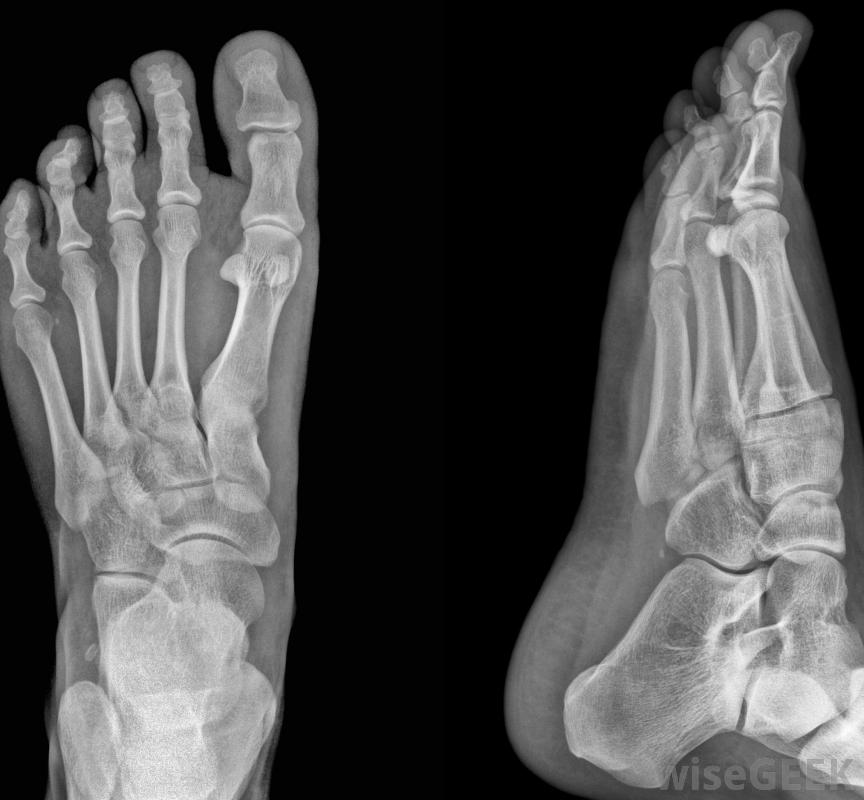

腳趾上的骨刺最常見的癥狀是什么(Most Common Symptoms of a Bone Spur on the Toe)?

骨刺,也被稱為骨贅,可以發生在骨骼系統的任何地方,但在腳中很常見。腳趾或腳后跟上的骨刺可能是由于周圍韌帶或軟骨的損傷或外傷,或者是由于老化和使用的自然結果。它們可能是由于骨的過度生長引起的,通常是在兩塊骨頭相遇的關節處腳趾骨刺的癥狀可能是患處疼痛、腫脹或觸痛骨刺可發生在任何腳趾上,但最常見于第五腳趾。在許多情況下,腳趾上的骨刺可能沒有任何癥狀。在某些情況下,患處確實會疼痛。骨贅引起的疼痛不是由"骨刺"本身引起的,但由于與另一塊骨頭、神經或軟組織的摩擦而產生。在極少數情況下,骨刺可能會折斷,卡在關節之間,從而導致關節不能活動。可以使用x光片來確認骨刺。治療腳趾上的骨刺的方法包括抗炎藥物治療、物理治療和用特殊的靴子或腳支撐暫時靜止不動。如果這些措施結合起來不起作用結果是,如果疼痛是慢性或嚴重的,或者影像學檢查顯示周圍神經、韌帶或肌腱受損,則可能需要手術。腳趾骨骨刺的手術通常很簡單,可能需要用手術緩沖液撫平骨刺,并移除全部或部分趾甲在某些情況下,骨刺是慢性腳痛的根本原因。在許多情況下,腳趾上的骨刺沒有任何癥狀如果疼痛很小或沒有疼痛,除了通過限制身體活動暫時讓腳休息之外,可能沒有什么需要做的。穿著舒適、合腳、不扭傷腳趾的鞋子也有助于減輕由骨刺引起的輕微不適患有骨刺的人在上下樓梯時可能會有困難。骨刺最常見于第五趾,盡管它們中的任何一個都可能發生腳趾上的骨刺可能需要手術,盡管手術通常很簡單。